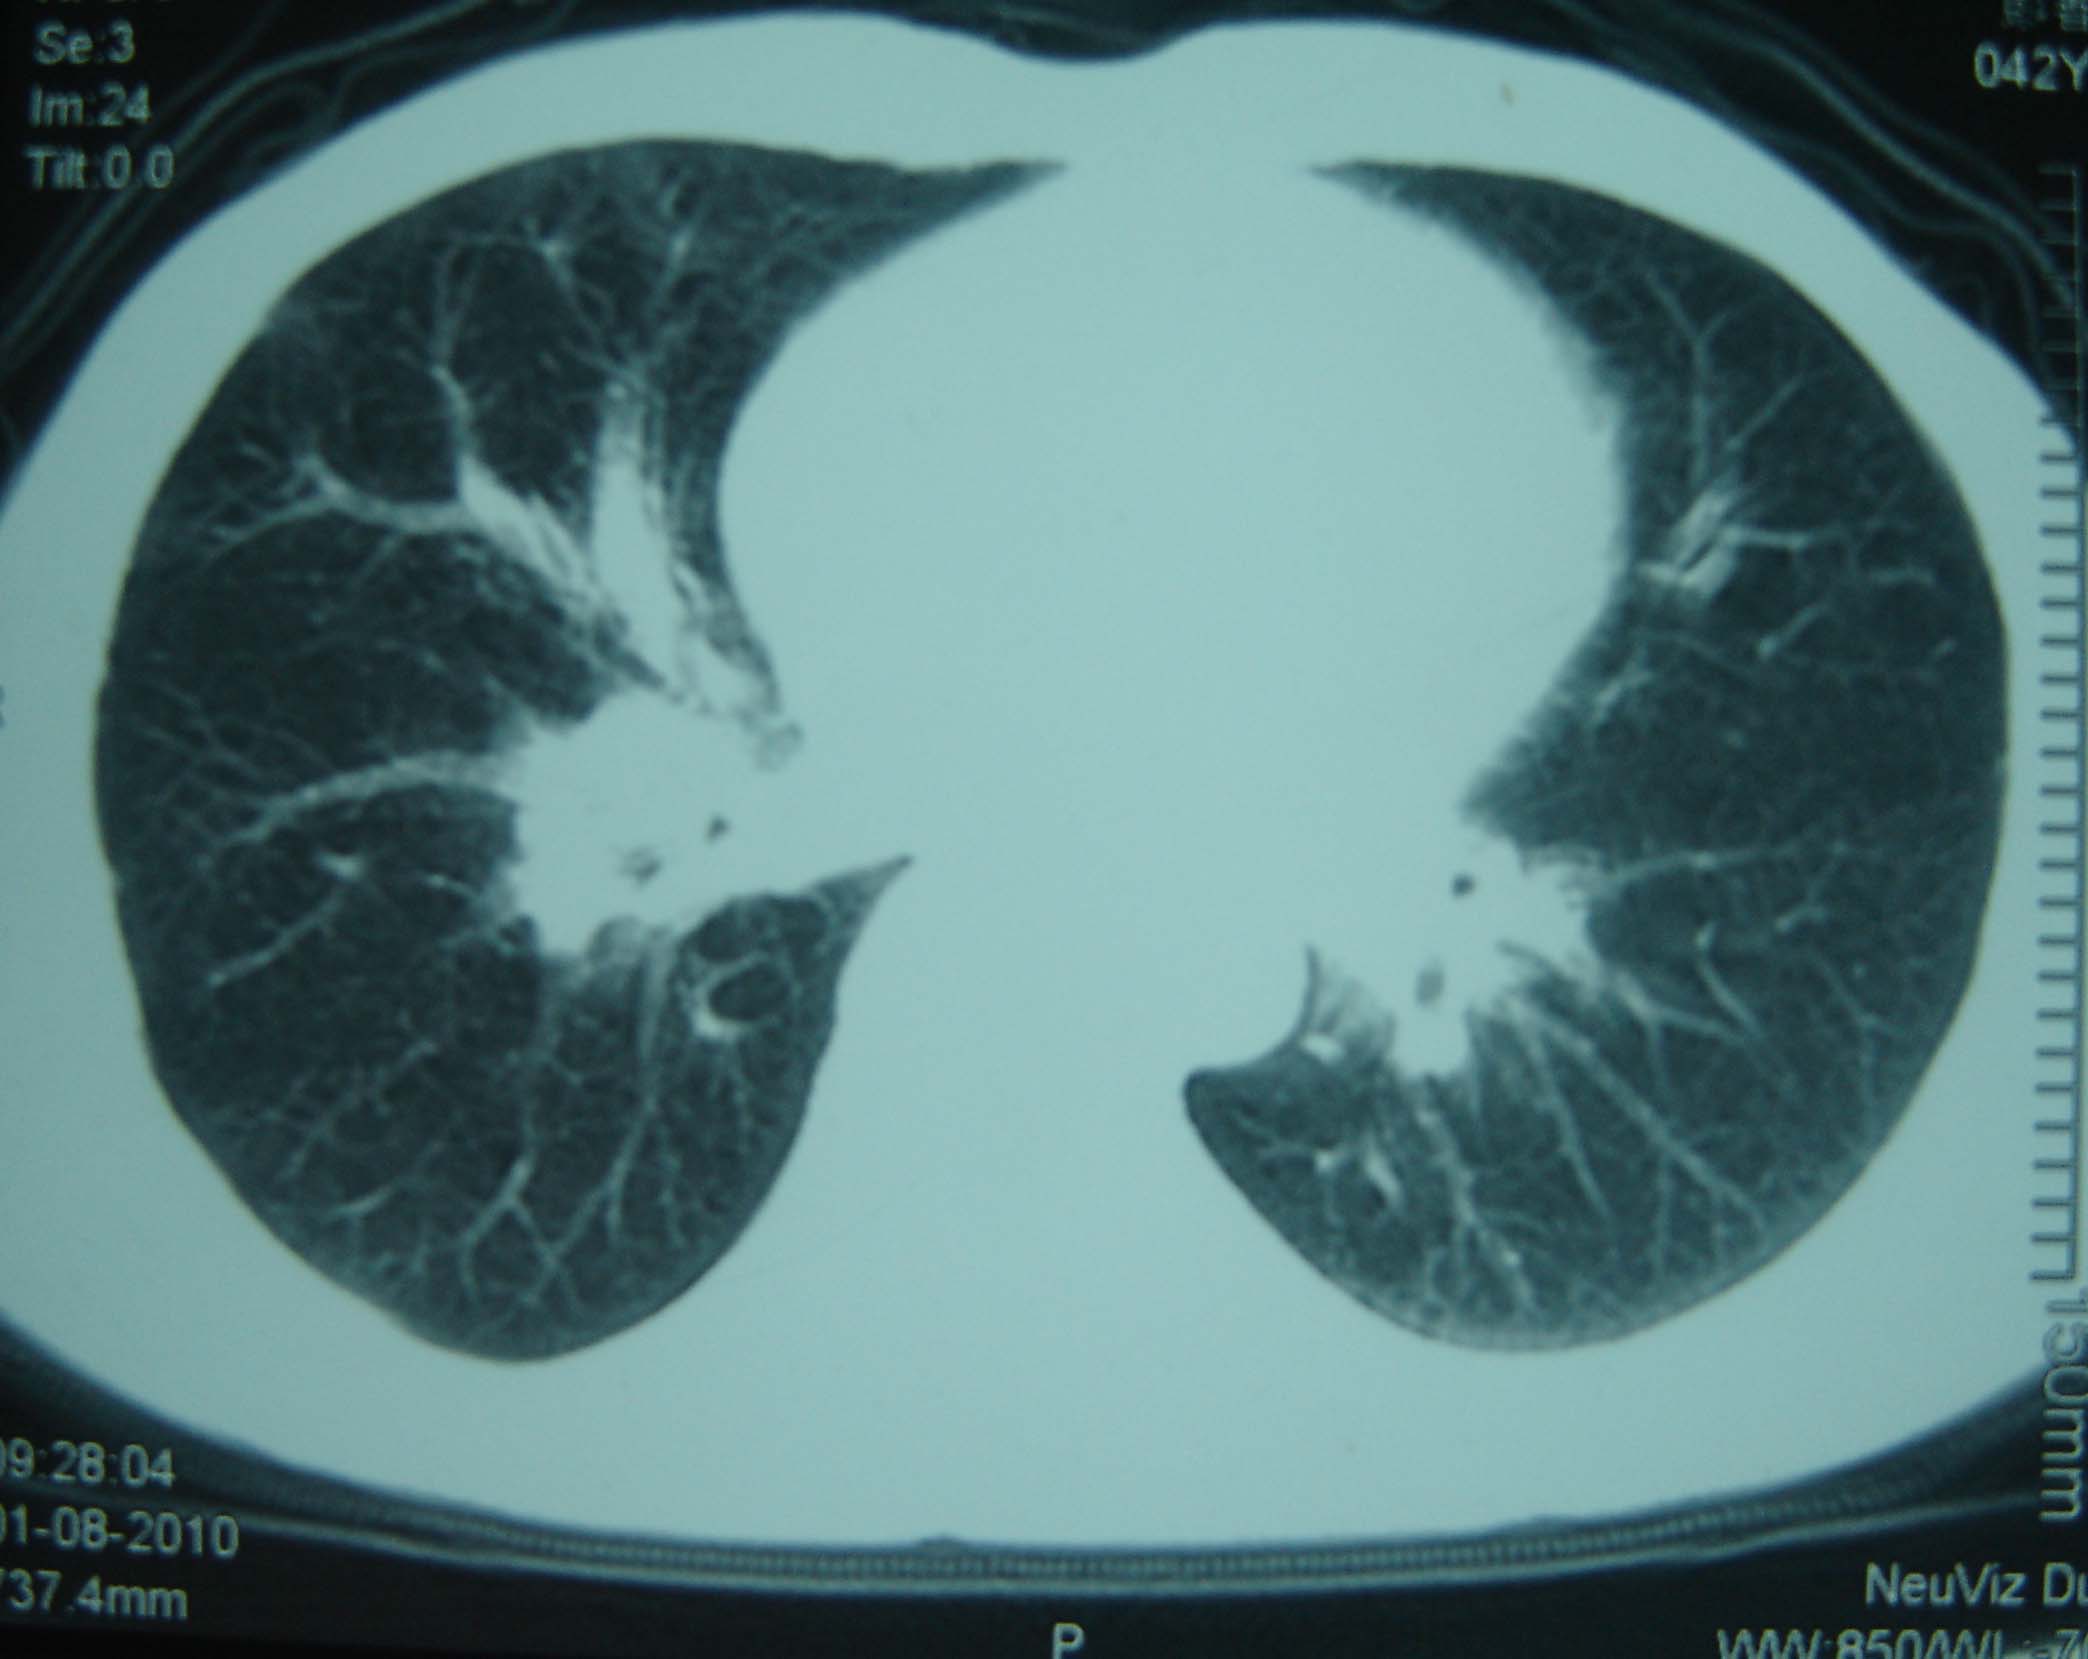

标题: CT25321:两肺多发结节 请会诊 [打印本页]

标题: CT25321:两肺多发结节 请会诊

男 、43岁,咳嗽胸痛,装修工,平时接触粉尘较多,有吸烟史10多年,纤维支气管镜检查未发现异常,胃镜、腹部b超检查亦未发现异常,颈部淋巴结活检未发现肿瘤细胞。

不能排除转移,如果不能找到原发灶,只有短期随访。

结节病?转移瘤?

结节病。

转移瘤?

1)考虑双肺及胸膜多发性转移瘤。2)肺气肿。

双肺结节病。